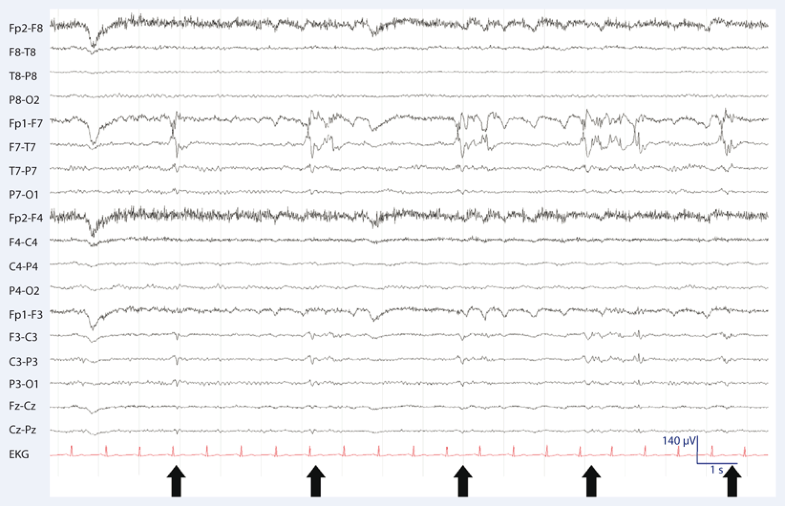

Das Elektroenzephalogramm kommt vorwiegend bei der Diagnose und Verlaufskontrolle von Epilepsie zum Einsatz, sowie bei der Überwachung von Patienten mit Bewusstseinsstörungen. Während eines EEG werden Elektroden am Kopf angebracht, die die Hirnströme messen. Die Elektroenzephalographie ist schmerzfrei und stellt für den Patienten unter.. Ein Standard-EEG ist für Diagnose, Verlaufsbeurteilung und Wahl der Therapie von Epilepsie und anderen Anfallskrankheiten unentbehrlich. Das EEG ist die einzige Methode, die eine epileptische Funktionsstörung direkt nachweisen kann. Es gibt aber auch Menschen mit Epilepsie, deren Standard-EEG normal ist oder nur unspezifische Veränderungen.

Sie heißt auch Hirnstromkurve oder Elektroenzephalogramm. Die Form, Frequenz und Höhe der Wellen zeigen dem Mediziner, ob und an welcher Stelle die Gehirnaktivität eventuell gestört ist. Ist auf dem Monitor keine Aktivität mehr erkennbar, können Ärzte mittels EEG auch den Hirntod feststellen. Ein EEG ist schmerzfrei.. Bei einem EEG (Elektroenzephalogramm) wird die elektrische Aktivität des Gehirns gemessen, ähnlich wie ein EKG (Elektrokardiogramm) die elektrische Aktivität des Herzens aufzeichnet.. Während der Untersuchung werden kleine Sensoren auf die Kopfhaut geklebt, um die elektrischen Signale aufzuzeichnen, die entstehen, wenn die Gehirnzellen miteinander kommunizieren.